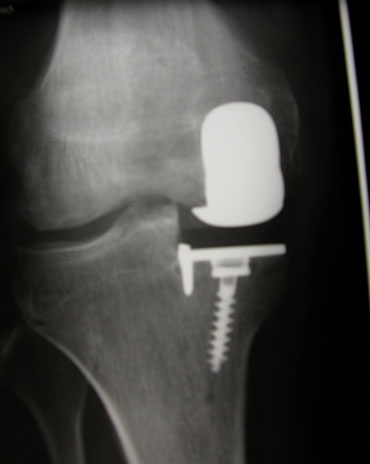

La prothèse uni-compartimentale (PUC) C’est une prothèse qui vise à effectuer le remplacement, soit du compartiment interne, soit du compartiment externe du genou, soit encore de l’articulation fémoro-patellaire c’est à dire la rotule. Ce sont donc des prothèses qui s’adressent à des personnes dont seul un des compartiments du genou est usé. L’avantage est de ne remplacer qu’une partie de l’articulation et ainsi de préserver le stock naturel d’os. L’autre avantage dont nous reparlerons est d’avoir des suites opératoires plus rapides et plus simples que la prothèse totale. La mobilité du genou est le plus souvent très proche de la normale.InconvénientsLe fait de garder les deux tiers de l’articulation naturelle expose à une reprise arthrosique sur les compartiments du genou laissés intacts ! On garde parfois quelques douleurs liées aux compartiments non prothèsés.A long termeUne reprise chirurgicale par une prothèse totale est toujours possible. Cette chirurgie secondaire est parfois rendue un peu plus difficile, une greffe est parfois nécessaire mais on trouve de l’os naturel sur place.

Radio de contrôle